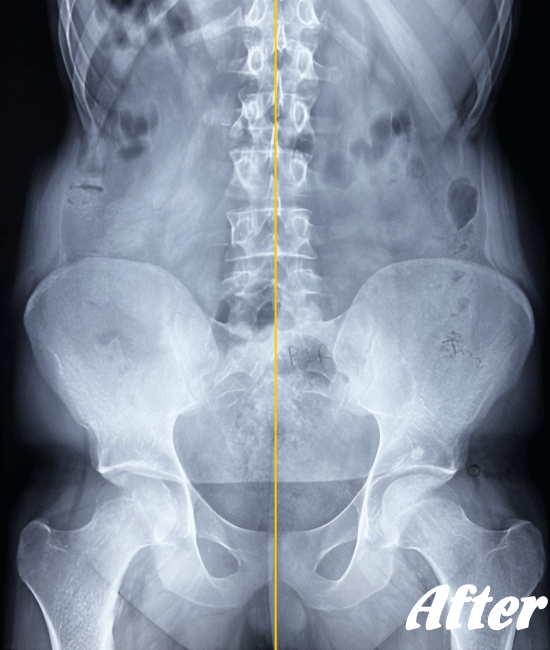

医療機関でも用いられているAKA療法を取り入れた施術により、身体に無理をかけず、ゆっくりと骨や関節の位置を解剖学的に正しい位置へ調整することで、痛みを取り除いていきます。慢性化した痛みも改善します。

多くの場合、骨盤の仙腸関節、腰の骨(腰椎)、そして足の付け根の股関節を調整すれば、痛みはなくなり、健康な状態に回復します。

ぎっくり腰程度であれば、初回の施術で腰が伸ばせる程度までには回復し、2回目の施術で残った痛みを取り除き、3回目で最後の違和感を解消します。